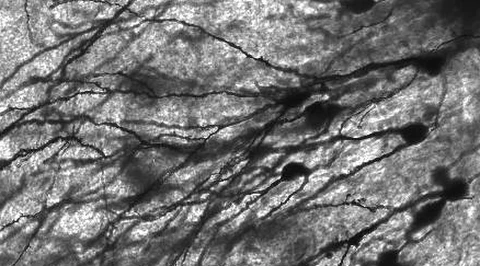

Nauka

Empatia doskonała